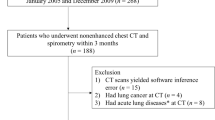

This study included ILD patients with CT scans at intervals of over 2 years between January 2015 and June 2021. Deep learning–based texture analysis software was used to segment ILD findings on CT images (fibrosis: reticular opacity + honeycombing cysts; total ILD extent: ground-glass opacity + fibrosis). Patients were grouped according to the absolute decline of predicted FVC (< 5%, 5–10%, and ≥ 10%) and ILD progression assessed by thoracic radiologists, and their quantification results were compared among these groups. The associations between quantification results and survival were evaluated using multivariable Cox regression analysis.